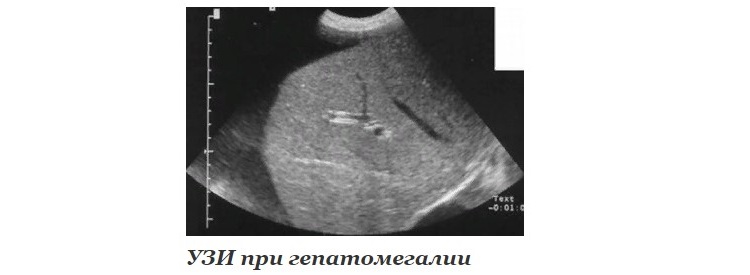

Инструментальная диагностика

Дает ценную информацию об изменениях паренхимы печени и рядом расположенных структур. Лучшими тестами я считаю:

- УЗИ (ультразвуковое исследование).

- КТ, МРТ (компьютерная и магнитно-резонансная томография).

- Пункционная биопсия – то есть взятие фрагмента ткани печени для исследования под микроскопом.

УЗИ, КТ и МРТ – это методы визуализации, то есть отображения исследуемых структур на экране аппарата или снимках. Они позволяют выявить как объемные образования (абсцессы, опухоли), так и признаки диффузных изменений печени (что свойственно, прежде всего, циррозу).